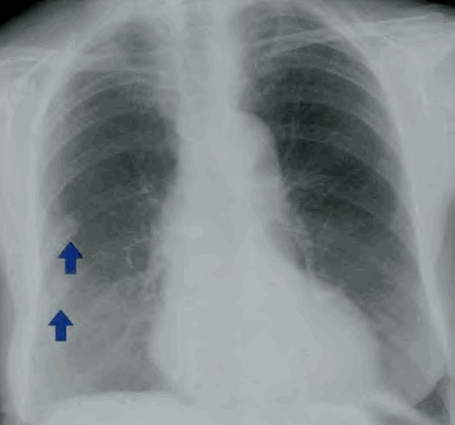

Усиление прикорневого легочного рисунка на рентгене – это симптомокомплекс специфических рентгеновских синдромов в легких, которые свидетельствуют о дыхательной недостаточности, пневмосклерозе легочных полей Рентгенограмма при усилении легочного рисунка с обеих сторон, фиброзные наложение на плевре (обозначены стрелками)

Усиление легочного рисунка в прикорневой зоне прослеживается при хроническом поражении бронхиального дерева, при котором снижена проходимость воздуха по бронхам. На фоне патологии развивается ослабление, усиление, обогащение кровоснабжения легких вдоль бронхов, но для развития данных изменений требуется время. В нижних легочных полях легкие имеют максимальную толщину, поэтому на рентгенограмме внизу наблюдается максимальное скопление легочных сосудов. Сложная картина обусловлена множеством переплетающихся, ветвящихся ветвей, которые наслаиваются и перекрещиваются. На определенный объем легочной ткани приходится определенное количество легочных сосудов. Если взять легочной квадрат, ограниченный ребрами, то на площадь приходится 2-4 ветви артерии. При увеличении количества этих элементов на квадратный объем говорят об усилении или обогащении легочного рисунка. Местами ветви легочных артерий перекрещиваются или наслаиваются друг на друга. Осевой или косой ход артерий прослеживается на рентгеновских снимках. При нарушении направления артерий говорят о деформации, которая может быть петлистой или ячеистой. При разных типах патологии наблюдается различные патологические изменения. Ячеистая деформация характерна для бронхоэктазов (полости выпячивания бронха), которые огибают ветви легочной артерии. Подобные полости хорошо прослеживаются при контрастировании, но на простой рентгенограмме не визуализируются. Бронхиальные разветвления наполнены воздухом, через которые рентгеновские лучи проходят без задержки. Перекрещивание сосудов формирует небольшие очаговые образования, которые сформированы тяжами сосудов. От инфильтративных или органических образований данные мелкие тени отличаются четкими контурами, небольшими размерами. Очаги изменяют интенсивность, форму, величину. Отдельные бронхиальные разветвления могут накладываться на легочной рисунок в норме. В прикорневых отделах на тень ветвей легочной артерии накладываются просветления, обусловленные бронхиальным деревом.

соединительной ткани. Соединительнотканные волокна накладываются на артерии, что создает интенсивные линейные тени на снимках. Располагаются по всей площади легочных полей – от прикорневых отделов до плащевидной зоны. Подобные изменения наблюдаются при нарушении гемодинамики. При увеличении давления в малом круге наблюдается усиление кровенаполнения легочных артерий. У больных с пороками сердца (митральный стеноз) наблюдается усиление кровоснабжения. Силикотуберкулезный пневмосклероз, силикотические изменения приводят к деформации легочного рисунка.